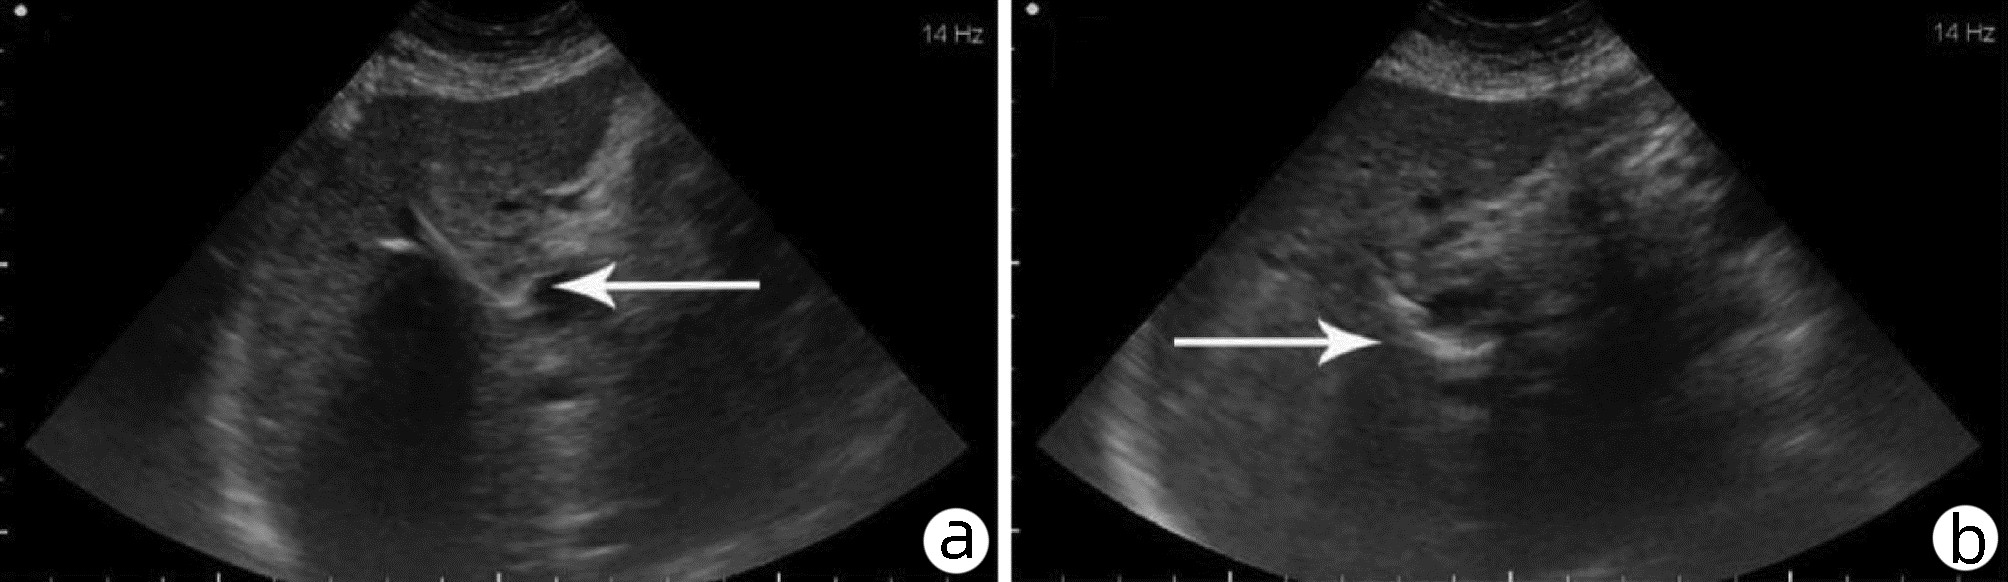

基于超声造影LI-RADS特征的肝细胞癌微血管侵犯列线图模型的构建及验证

2022, 38(11): 2520-2525. DOI: 10.3969/j.issn.1001-5256.2022.11.016

摘要(882) HTML (345) PDF (2938KB)(63)

摘要:

目的  基于肝细胞癌(HCC)患者的超声造影(CEUS)肝脏成像报告和数据系统(LI-RADS)特征建立预测微血管侵犯(MVI)的列线图模型并进行验证。  方法  选取2017年1月—2020年7月在江苏大学附属武进医院确诊的HCC患者共262例,按照1∶ 1比例随机分为建模组和验证组各131例,以术后镜下病理结果确诊MVI,其中建模组MVI 70例和验证组MVI 56例。采用超声造影评估两组的LI-RADS特征。两组间计量资料比较采用独立样本t检验;两组间计数资料比较采用χ2检验。采用单因素和多因素Logistic回归分析筛选建模组MVI的危险因素;绘制受试者工作特征曲线(ROC曲线),计算模型预测MVI的曲线下面积(AUC),评估预测准确度;应用决策曲线分析模型的一致性,比较模型预测MVI的校正曲线与标准曲线的离散度。  结果  建模组与验证组患者的临床资料和CEUS检查结果比较,差异均无统计学意义(P值均>0.05)。单因素分析显示,与MVI阴性患者相比,MVI阳性患者血清AFP水平显升高,肿瘤直径增大,LI-RADS显示LR-5“后出”和LR-M“先出”增多,LI-RADS分级较高,差异均有统计学意义(P值均<0.05)。多因素分析显示,AFP 20~400 ng/mL(OR=2.65,P<0.001)、AFP≥400 ng/mL(OR=3.98,P<0.001)、肿瘤直径≥30 mm(OR=2.12,P<0.001)和CEUS显示LR-M(OR=3.24,P<0.001) 是MVI的独立危险因素。ROC曲线显示,列线图预测建模组和验证组MVI的AUC分别为0.867和0.821。列线图模型的一致性指数C-Index为0.765(95%CI:0.701~0.834)。在建模组和验证组,列线图模型的预测校准曲线与标准曲线均接近。  结论  利用CEUS得出LI-RADS,并结合AFP和肿瘤直径建立的列线图模型有较好的应用价值,有助于指导临床术前筛选MVI高危患者,制订恰当的手术方案。